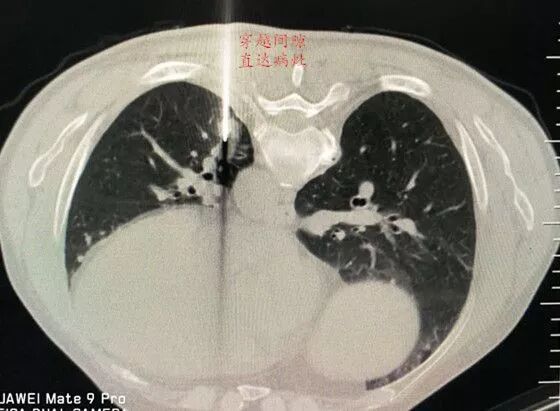

前縱隔結節(jié),直經約15mm,病灶紅色字體標示。

前有胸骨C,后有主肺動脈A、B,兩側有胸廓內動脈D、E遮擋,形成合圍之勢。

選擇右成角入路,穿越胸骨與主動脈間隙,該間隙僅僅10mm,并避開右胸廓內動脈,精細操作,先置入導針

順利規(guī)避大血管進入靶病灶,激發(fā)活檢槍后完成病變組織切割取材。